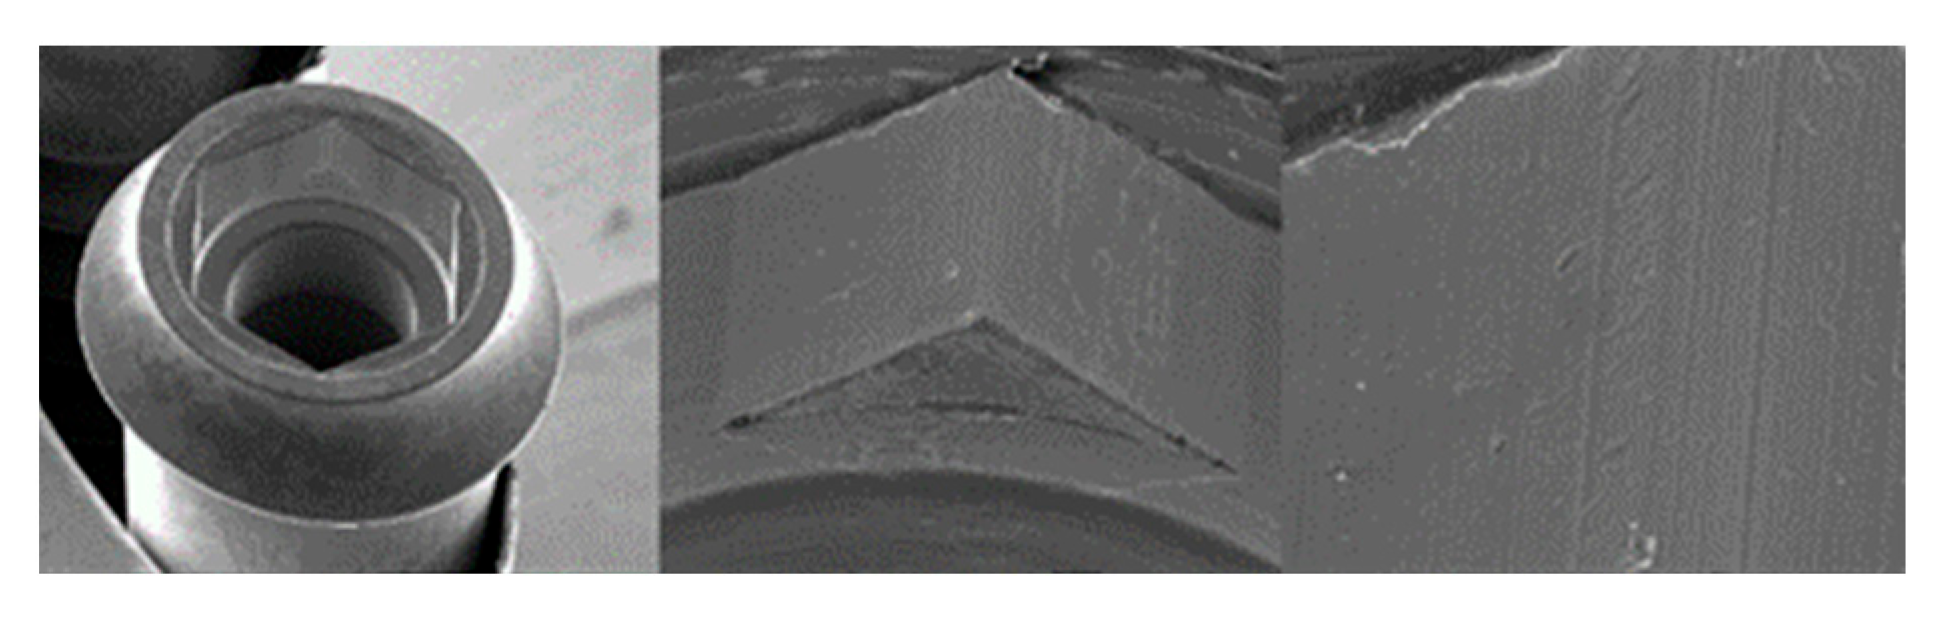

3.1. SEM

3.1.2. Essential Implants

4.1. SEM Evaluation